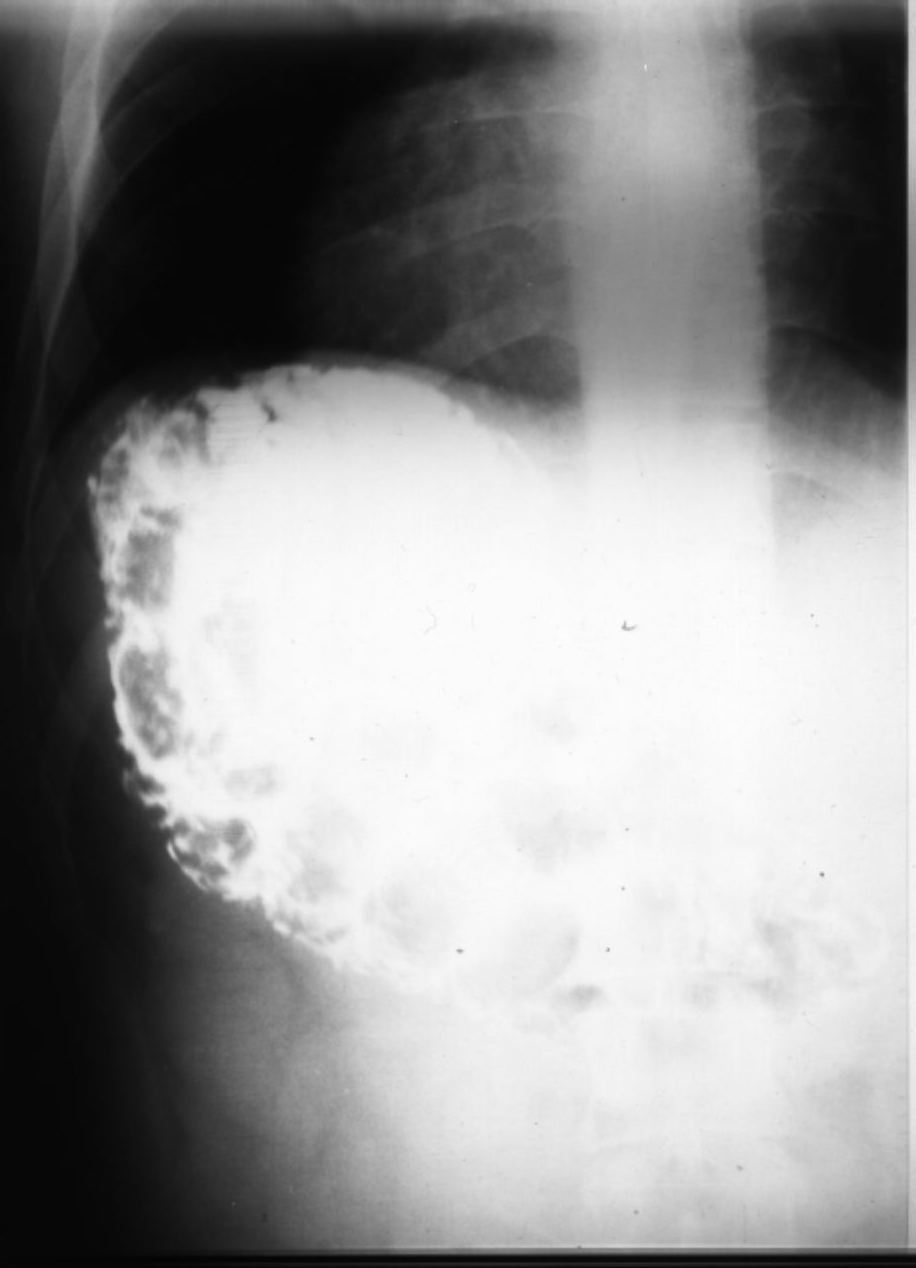

10. 4. Intoxicación por drogas de abuso

Figura 6